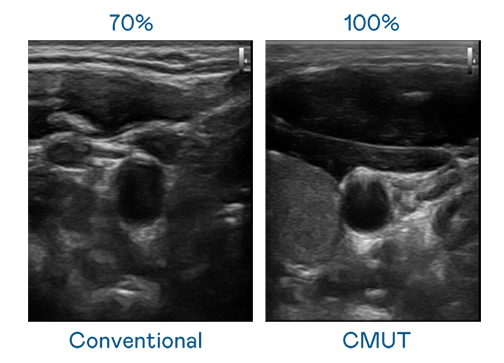

CMUT 技术是一种用电容式微机电元件来产生超音波讯号的技术。与传统 PZT 压电式技术相比,CMUT 频宽增加 30%,更宽频的超音波讯号让影像解析度大幅提升,是实现高影像品质医疗超音波扫描、促进精准医疗发展的关键技术。

大频宽带来超清晰影像

超音波影像的解析度高低,首先取决于探头能发出的讯号频宽。九游会(J9) CMUT 可提供高清晰的超音波讯号,提供高频宽、高灵敏度、影像纹理细节更高的超音波影像,协助医护人员缩短影像判读时间及利用精准的医疗影像进行诊断。